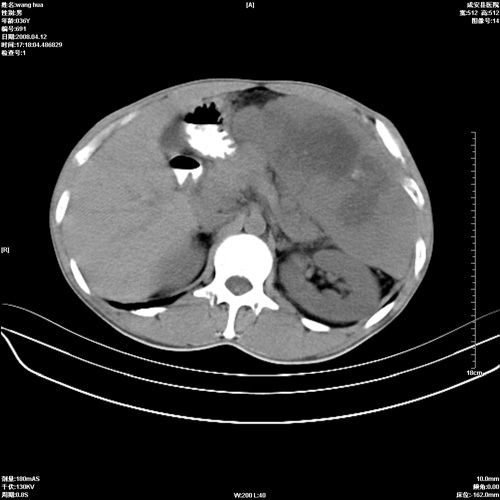

标题: CT12809:男36岁,自感上腹胀5天,B超诊断为脾肾之间占位,血 [打印本页]

标题: CT12809:男36岁,自感上腹胀5天,B超诊断为脾肾之间占位,血

请各位老师先分析一下定位 明天做增强

确实需要强化!先大胆预测一下,来源于脾脏的占位,血管瘤或淋巴瘤可能性大。

脾脏肿瘤,有钙化,增强再说

脾脏病变,密度不均,可见钙化,考虑脾血管瘤,建议增强

脾脏明显增大,其内见巨大低密度灶,境界不清,病史较短,考虑恶性病变脾血管内皮细胞肉瘤可能。建议增强扫描与脾脏淋巴瘤及血管瘤鉴别。